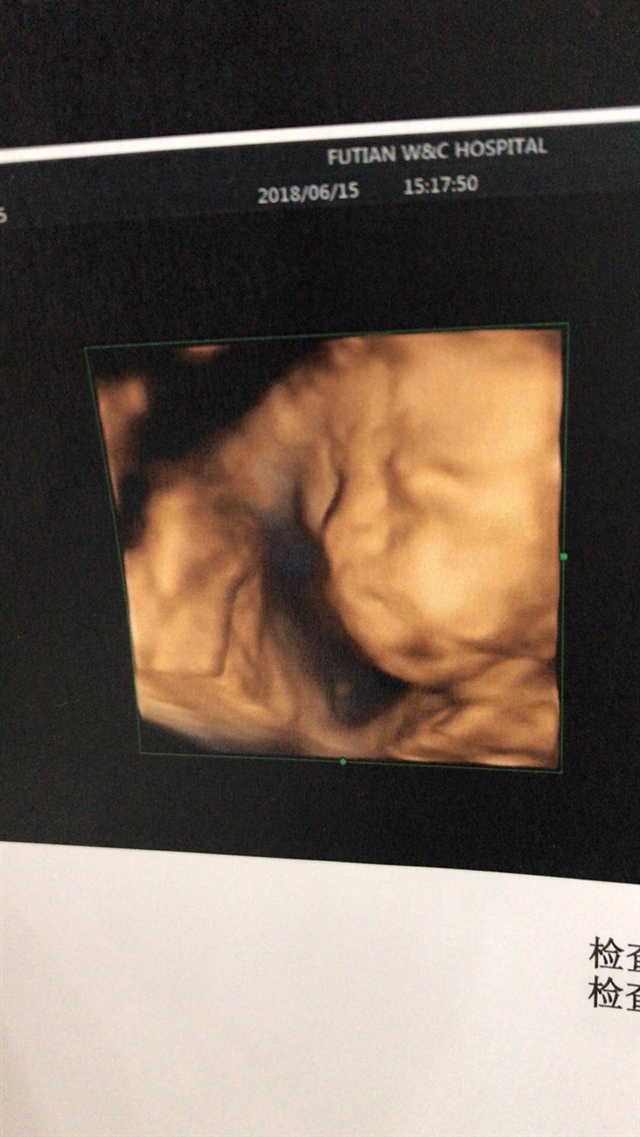

生命滋味[帖主]:怎么看咧